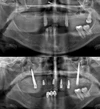

نقص الأسنان

علاج الزرعات السنية

التهاب ما حول الزرعة السنية (Periimplantitis)

أكياس الفك